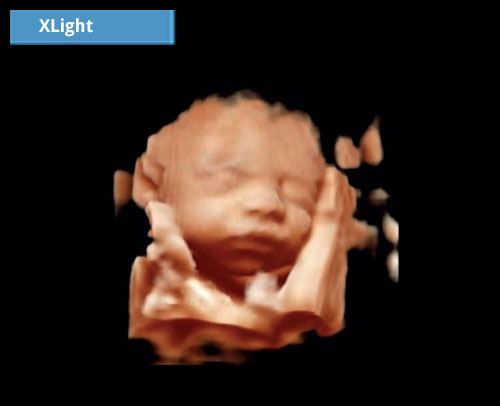

XLight: Pokročilý algoritmus pro zlepšení volumetrické kvality vykreslování.